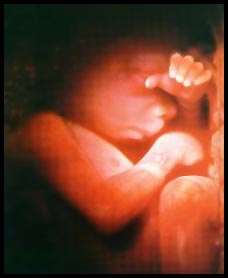

15 haftalık bebek Bebeğinizin kemikleri iyice sertleşmesine rağmen, derisi hala çok ince ve deri altından damarları görünüyor. Kafa derisi üzerinde ince ve ipeksi tüyler belirginleşmeye başladı. 12 cm’lik koca bir bebek olarak, artık yüz ifadeleri bile var.